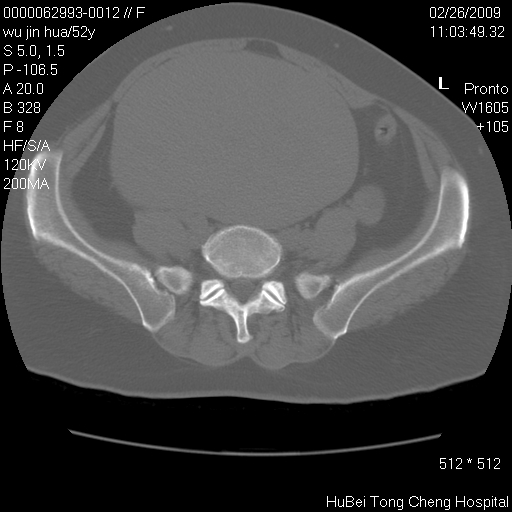

依据平片“腰椎退行性改变”报告,作椎间盘ct扫描时发现:

盆腔彩超报告:子宫肌瘤。(或许也漏诊了!)

影像表现:盆腹腔巨大占位,内密度均匀,边界清,未做强化。

来源:考虑来源于腹膜后肿瘤。

性质:以肉瘤可能性大。